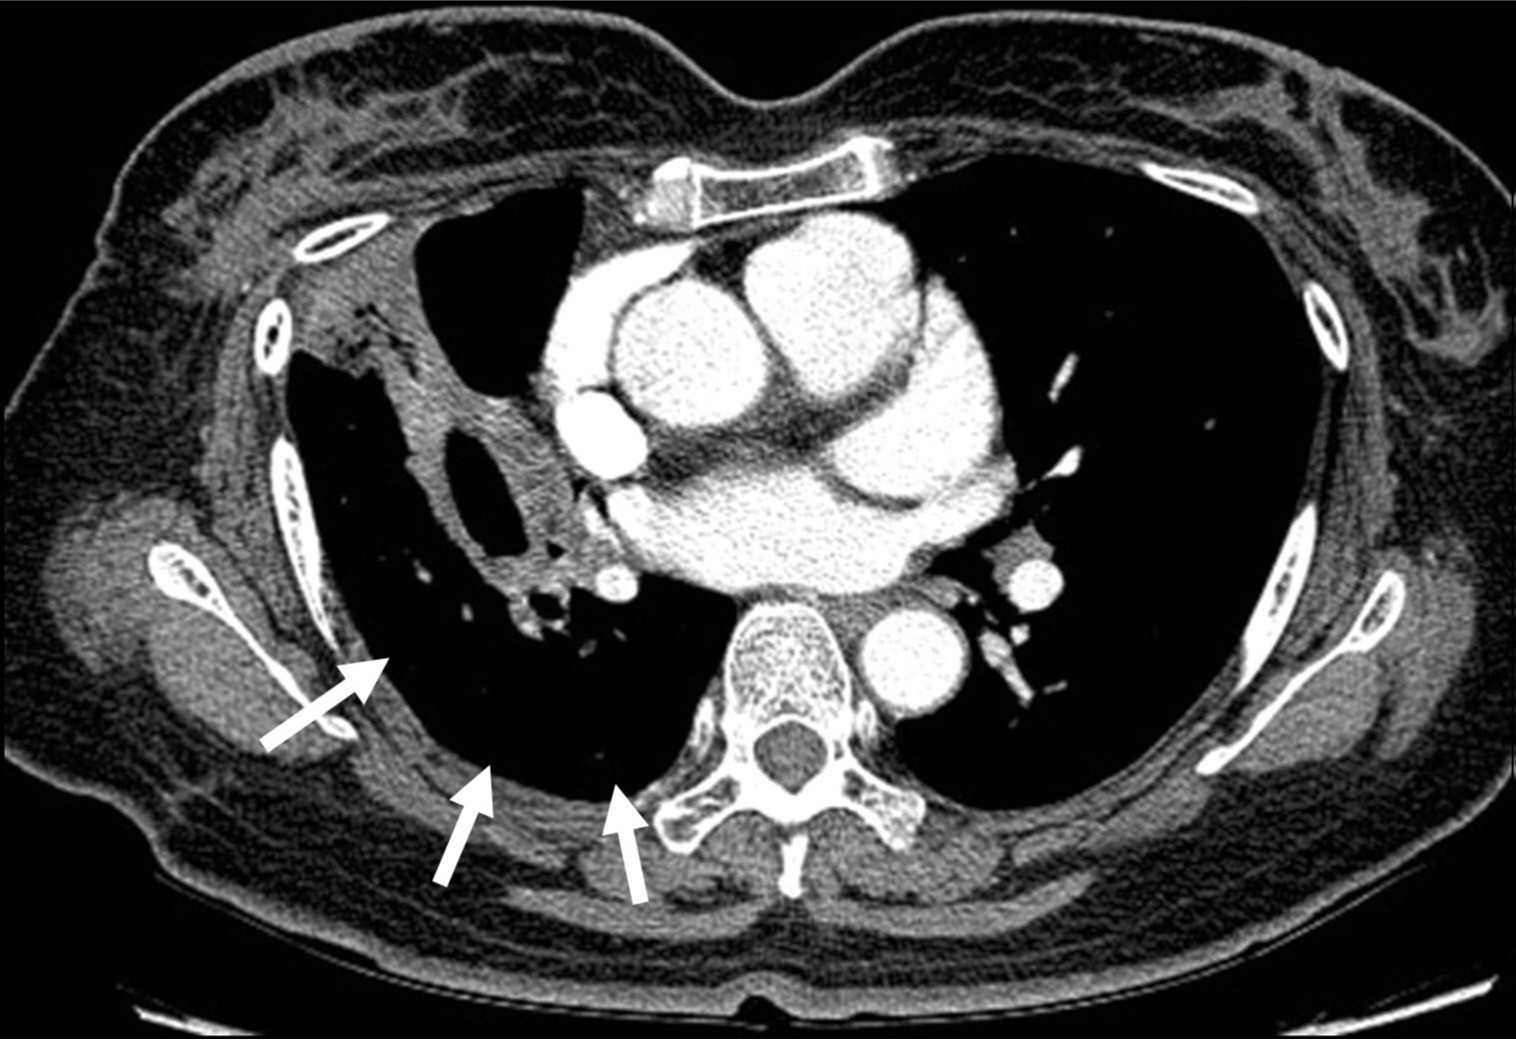

3주 후 시행한 흉부 CT에서 가성동맥류는 완전 소실되었고, 색전 원위부의 우하엽은 폐동맥 혈류가 차단되었음에도 aeration이 잘 유지되었다(Fig. 5).

Fig. 5. A

Fig. 5A, B. The axial images (A, B) of Chest CT scan 3 weeks after embolization show disappearance of the pseudoaneurysm and well-preserved aeration (arrows) of the distal right lower lobe.

Fig. 5. B